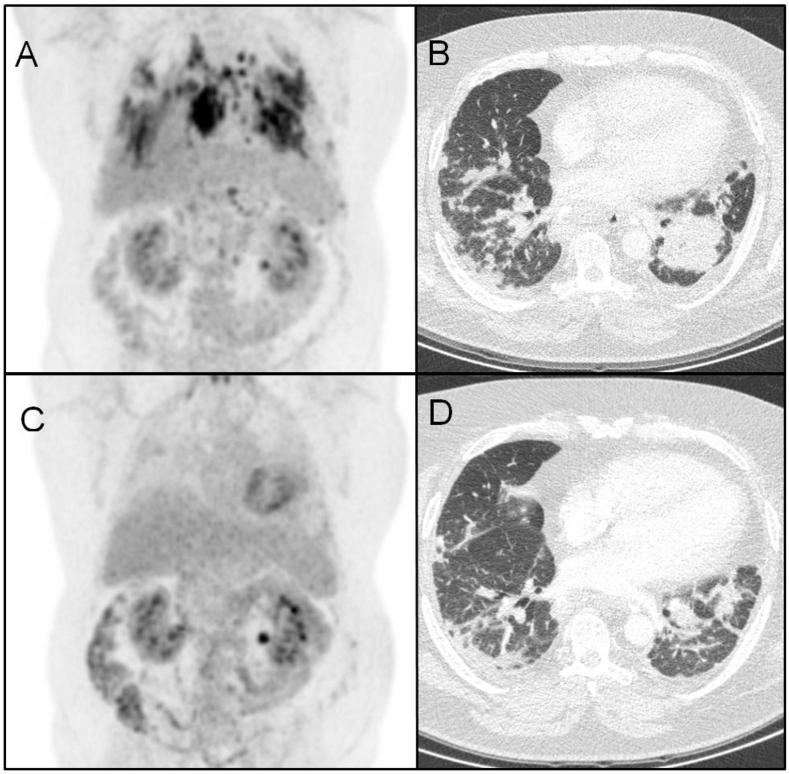

A diagnosis of silicosis is made on the basis of exposure and typical radiological findings, according to the ILO's International Classification of Radiographs of Pneumoconiosis. Radiological patterns of silicosis can, however, resemble sarcoidosis. Sarcoidosis is a multi-systemic disorder of unknown etiology, although a role for initiating inorganic triggers such as metals or silica has been suggested. In this case report, we illustrate a patient previously diagnosed with silicosis based on exposure and radiological features, progressive under immunosuppressive treatment. In view of these findings, an open lung biopsy was performed and revealed sarcoidosis. The patient was effectively treated with infliximab. Further analysis showed the presence of silica in the granulomas. Sensitization to silica was also demonstrated, suggesting an association between silica exposure and sarcoidosis in this patient.

根据国际劳工组织的《尘肺病X线诊断国际分类》,矽肺病的诊断基于接触史和典型的放射学表现。然而,矽肺病的放射学模式可能与结节病相似。结节病是一种病因不明的多系统疾病,尽管有人提出金属或二氧化硅等引发无机触发因素可能起作用。在本病例报告中,我们阐述了一名先前根据接触史和放射学特征被诊断为矽肺病的患者,在免疫抑制治疗下病情进展。鉴于这些发现,进行了开放性肺活检,结果显示为结节病。该患者接受英夫利昔单抗治疗后病情得到有效缓解。进一步分析显示肉芽肿中存在二氧化硅。同时也证实了对二氧化硅的致敏反应,表明该患者的二氧化硅接触与结节病之间存在关联。